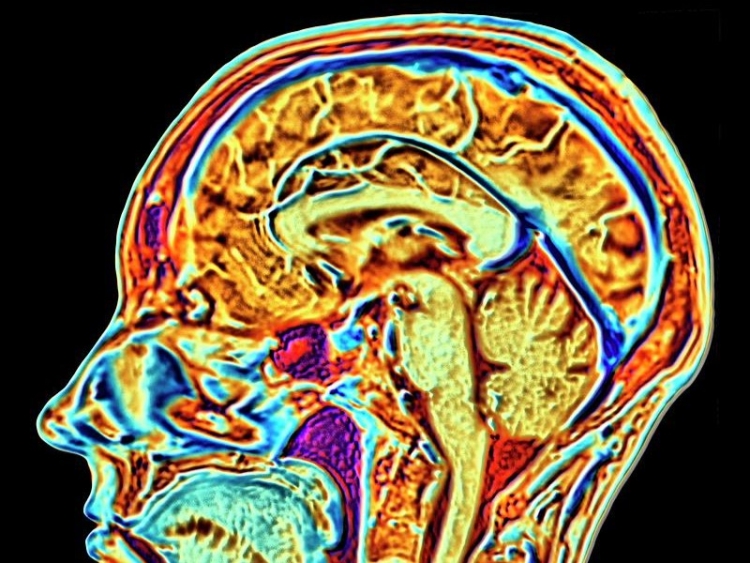

Tech tycoon Elon [look at me] Musk says his Neuralink firm has stuck one of its wireless brain chips in a human for the first time.

The firm aims to link human brains to computers and wants to help sort out tricky brain problems.

This lets them start the six-year study where a robot is used to stick 64 bendy threads, thinner than a human hair, onto a part of the brain that controls movement.

The firm says that these threads let its trial implant - powered by a battery that can be charged without wires - record and send brain signals to an app that works out how the person wants to move.